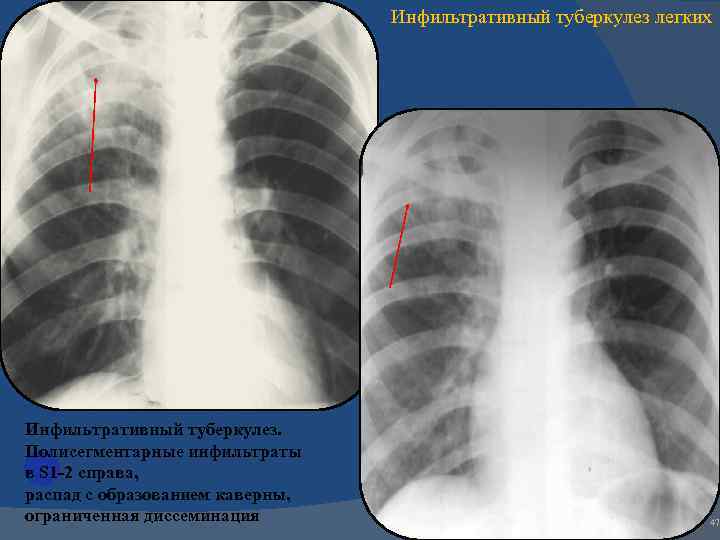

Иллюстрации по теме очагового и инфильтративного туберкулеза

Раздел: Фотодневник открытий